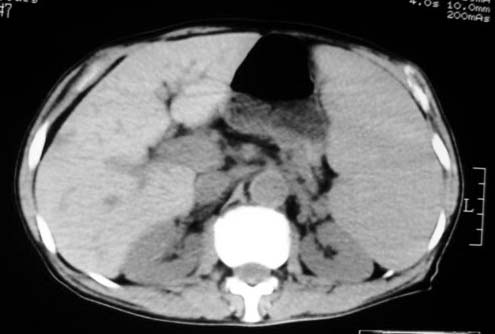

以下是引用dyqct在2007-4-20 16:38:00的发言:[br]考虑:1、巨脾;[br] 2、肝内多发低密度,首先考虑转移瘤;[br] 3、胆囊多发结石。

以下是引用andymaomao在2007-4-20 16:47:00的发言:[br]肝脾增大,肝内胆管扩张,且可见多发小囊性低密度灶,胆囊窝区高密度影,手术化疗病史,贫血....[br]1.肝脾大及贫血与术后化、药疗有关;[br]2.胆囊窝区高密度影,术后改变?肝内胆管扩张,积液?[br]3.肝内多发低密度灶,性质?建交增强